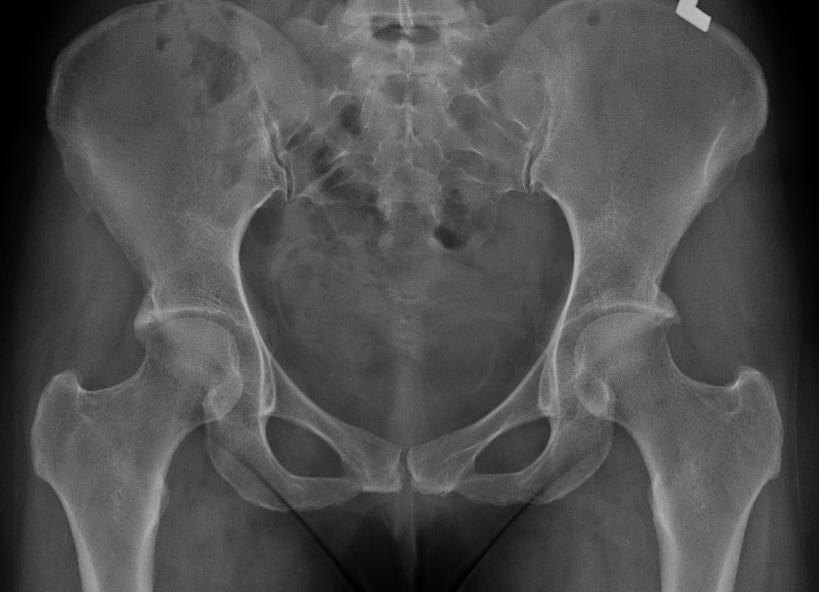

Bilateral pincer

Ossified labrum

Os acetabuli